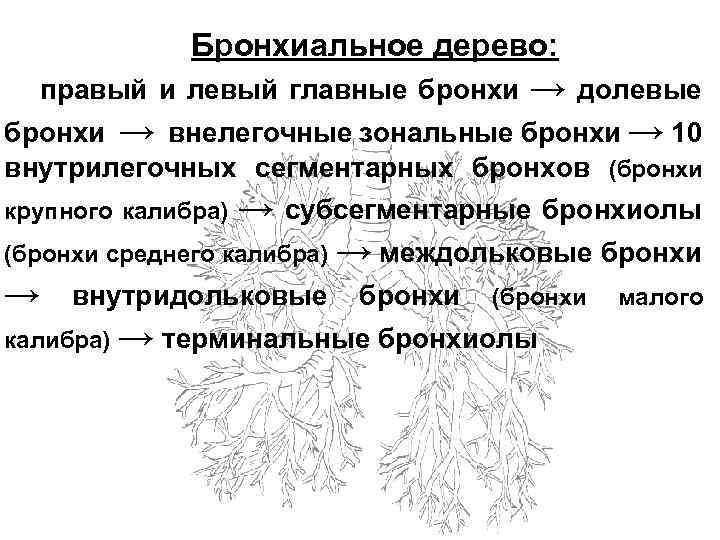

Трахея на нижнем конце делится на 2 ветви, образуя главные бронхи, которые входят в состав корней легких. Главными бронхами начинается бронхиальное дерево. Оно подразделяется на внелегочную и внутрилегочную часть.

Бронхиальное дерево: → долевые → внелегочные зональные бронхи → 10 правый и левый главные бронхи внутрилегочных сегментарных бронхов (бронхи крупного калибра) → субсегментарные бронхиолы (бронхи среднего калибра) → внутридольковые калибра) → междольковые бронхи (бронхи → терминальные бронхиолы малого